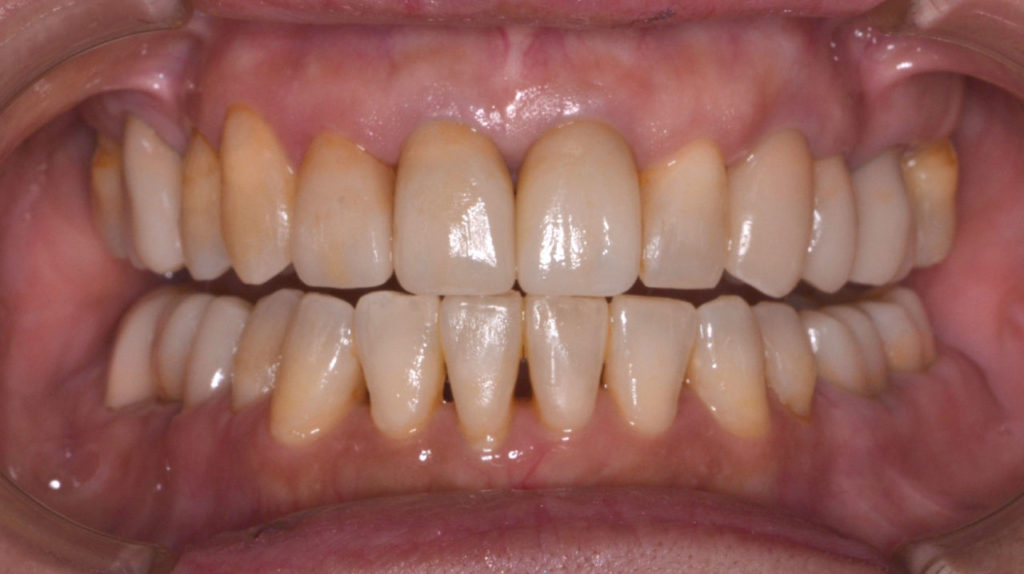

治療後

奥歯が干渉している状態

矯正を伴う咬合再構成を行った患者さんです。アンテリア ガイダンスが取れるようになりました。